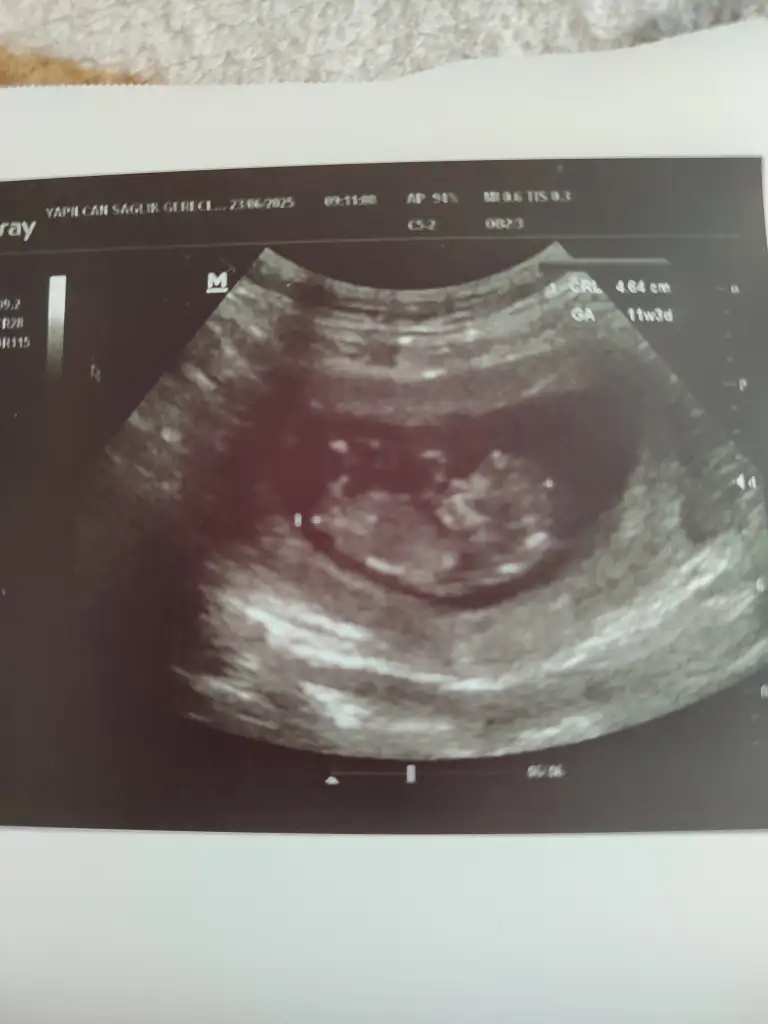

Ayrı haftalarda çekilmiş görüntüler. Karından ultrason. İlki 5hafta 5gün, ikincisi 7hafta 3gün.Nerden bu goruntu? bebek sağdamı soldamı ? bir de ıkı goruntu neden farklı

Bence kız içime doğdu vede kese konumundan dolayı ama kese şekli tahmini için erkenKızlar cinsiyet tahmini yapabilecek olan var mı?

Kese konumuna göre nasıl tahmin yaptınız merak ettim de :) bende meraklıyım birazBence kız içime doğdu vede kese konumundan dolayı ama kese şekli tahmini için erken

Üç kere erkek bebeğe hamile kaldım hepsi daha üstte sağa yakın konumdaydı tesadüf mü bilmiyorum ona istinaden dedim az sabredin çok gğzel heyecanlarKese konumuna göre nasıl tahmin yaptınız merak ettim de :) bende meraklıyım biraz